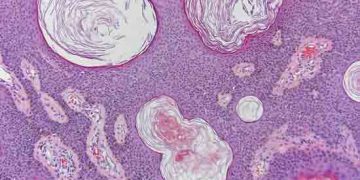

Yalancı Boynuz Kistleri, hiperplastik ve hiperkeratotik epidermisin iç içe geçmesi sonucu oluşan kist benzeri yapılar. Hiperplastik veya neoplastik epidermis dermatozislerinde ...